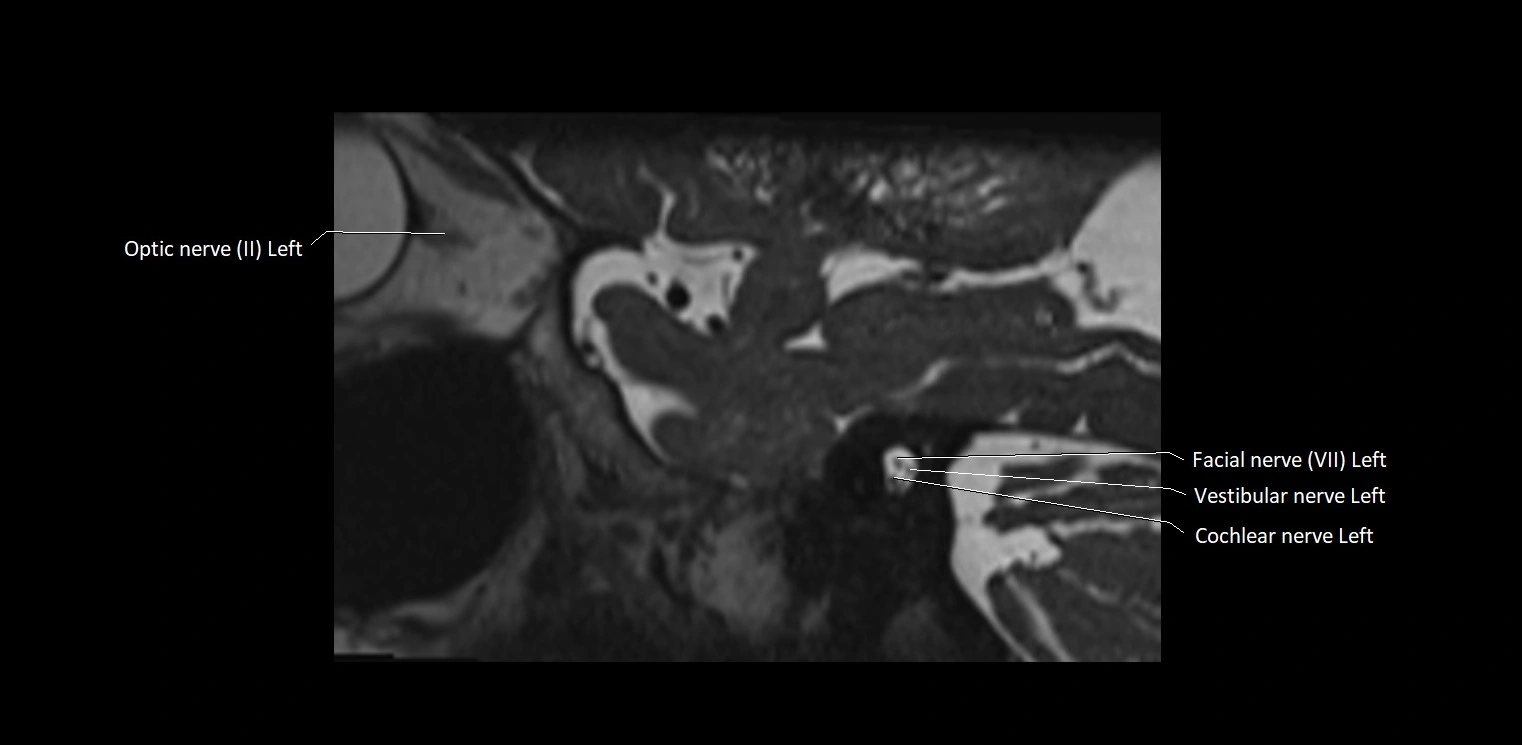

MRI Appearance

• The abducens nerve is a small, thin, linear structure

• Best visualized on high-resolution T2-weighted 3D MRI sequences (e.g., FIESTA or CISS)

• Seen as a hypointense (dark) line running from the brainstem at the pontomedullary junction, traversing the prepontine cistern, and entering Dorello’s canal under the petrosphenoidal ligament, then into the cavernous sinus, and finally the orbit

• May be challenging to visualize in standard MRI due to its small size

• Pathology may be inferred by absence, displacement, or enhancement of the nerve

MRI images

image